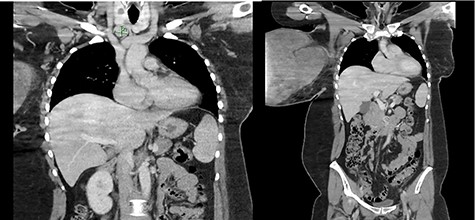

The right breast mass with two ulcerating wounds at centre, stretched-out erythematous skin.

The wound swab showed heavy growth of Staphylococcus aureus susceptible to Flucloxacillin. On ultrasonography, the right breast was completely replaced by a massive solid, heterogenous mass. It demonstrated internal vascularity and numerous cleft cystic spaces and leaf-like internal architect. Mammogram was not feasible due to the incompressible nature of the right breast, patient discomfort and the size of the lesion. A chest computed tomography was ordered for staging/metastatic workup and preoperative planning. Multiple enlarged right axillary lymph nodes measuring up to 12 mm and a 19 mm lymph node in the right supraclavicular region were noted with no distant metastasis (Fig. 2). The core biopsy showed features of spindle cell lesion with the differentials being borderline PT versus metaplastic carcinoma.